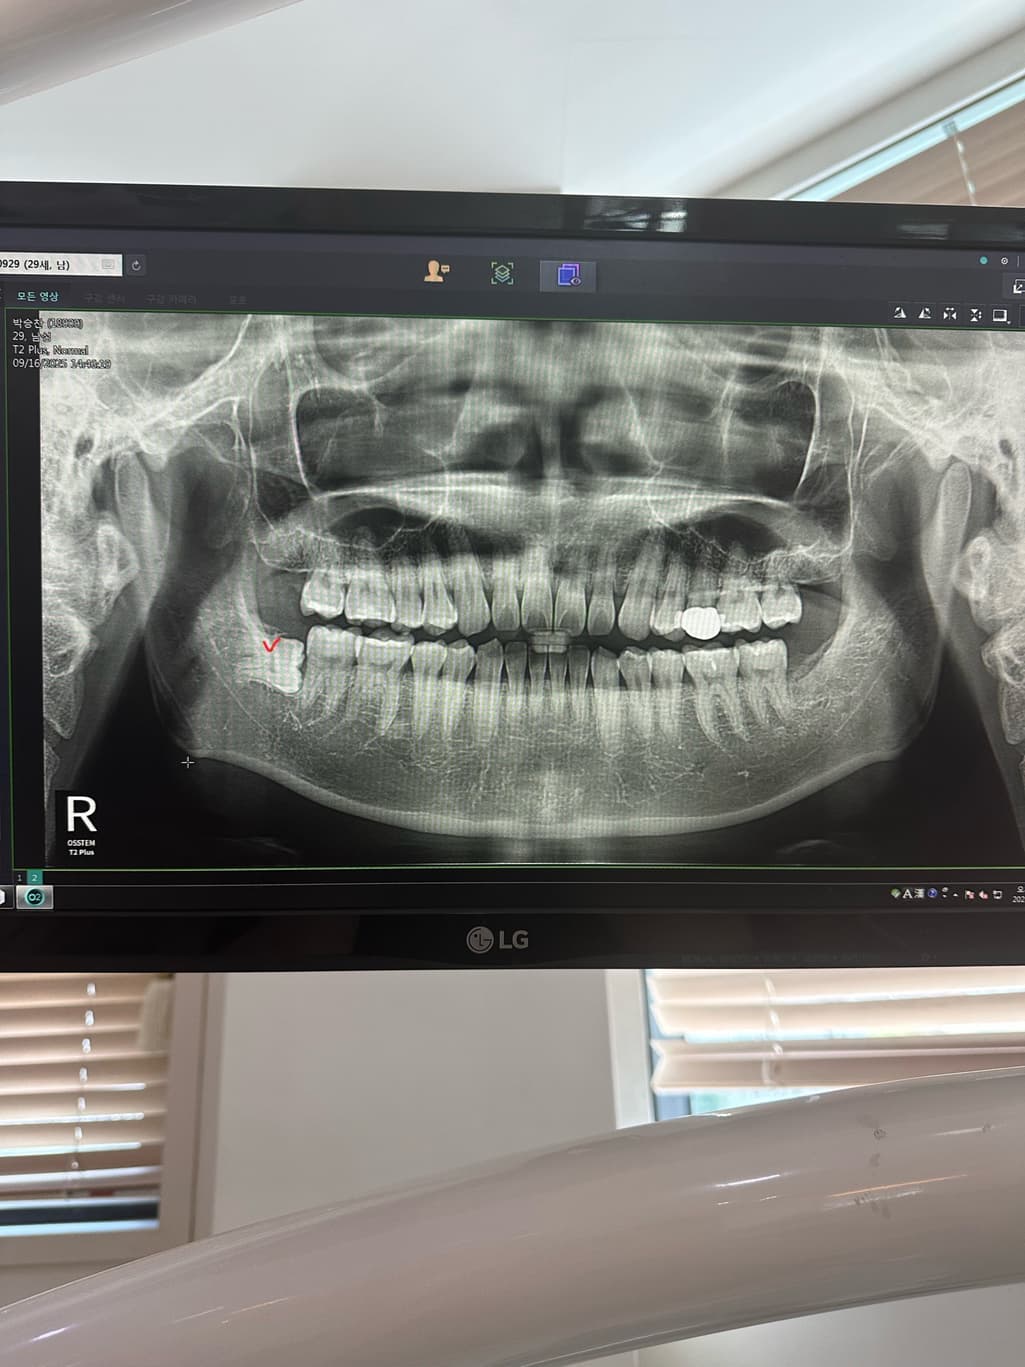

완전옆으로 누여있는 사랑니 였고 이틀이후 얼굴에 멍이 올라올정도 였으며

사랑니의 매복된 정도를 봤을 때 뼈 삭제량도 많았을 것이라 붓기나 통증이 더 오래갈 것 같습니다.

사랑니 매복이 깊어서 잇몸 절개도 많이 햇고, 잇몸뼈 삭제를 많이 한경우에는 붓기가 몇일갈수도 있습니다.

매복사랑니 발치 과정에서 뼈도 다소 삭제하고 그랬다면 붓기는 일주일 이상 가기도 합니다.